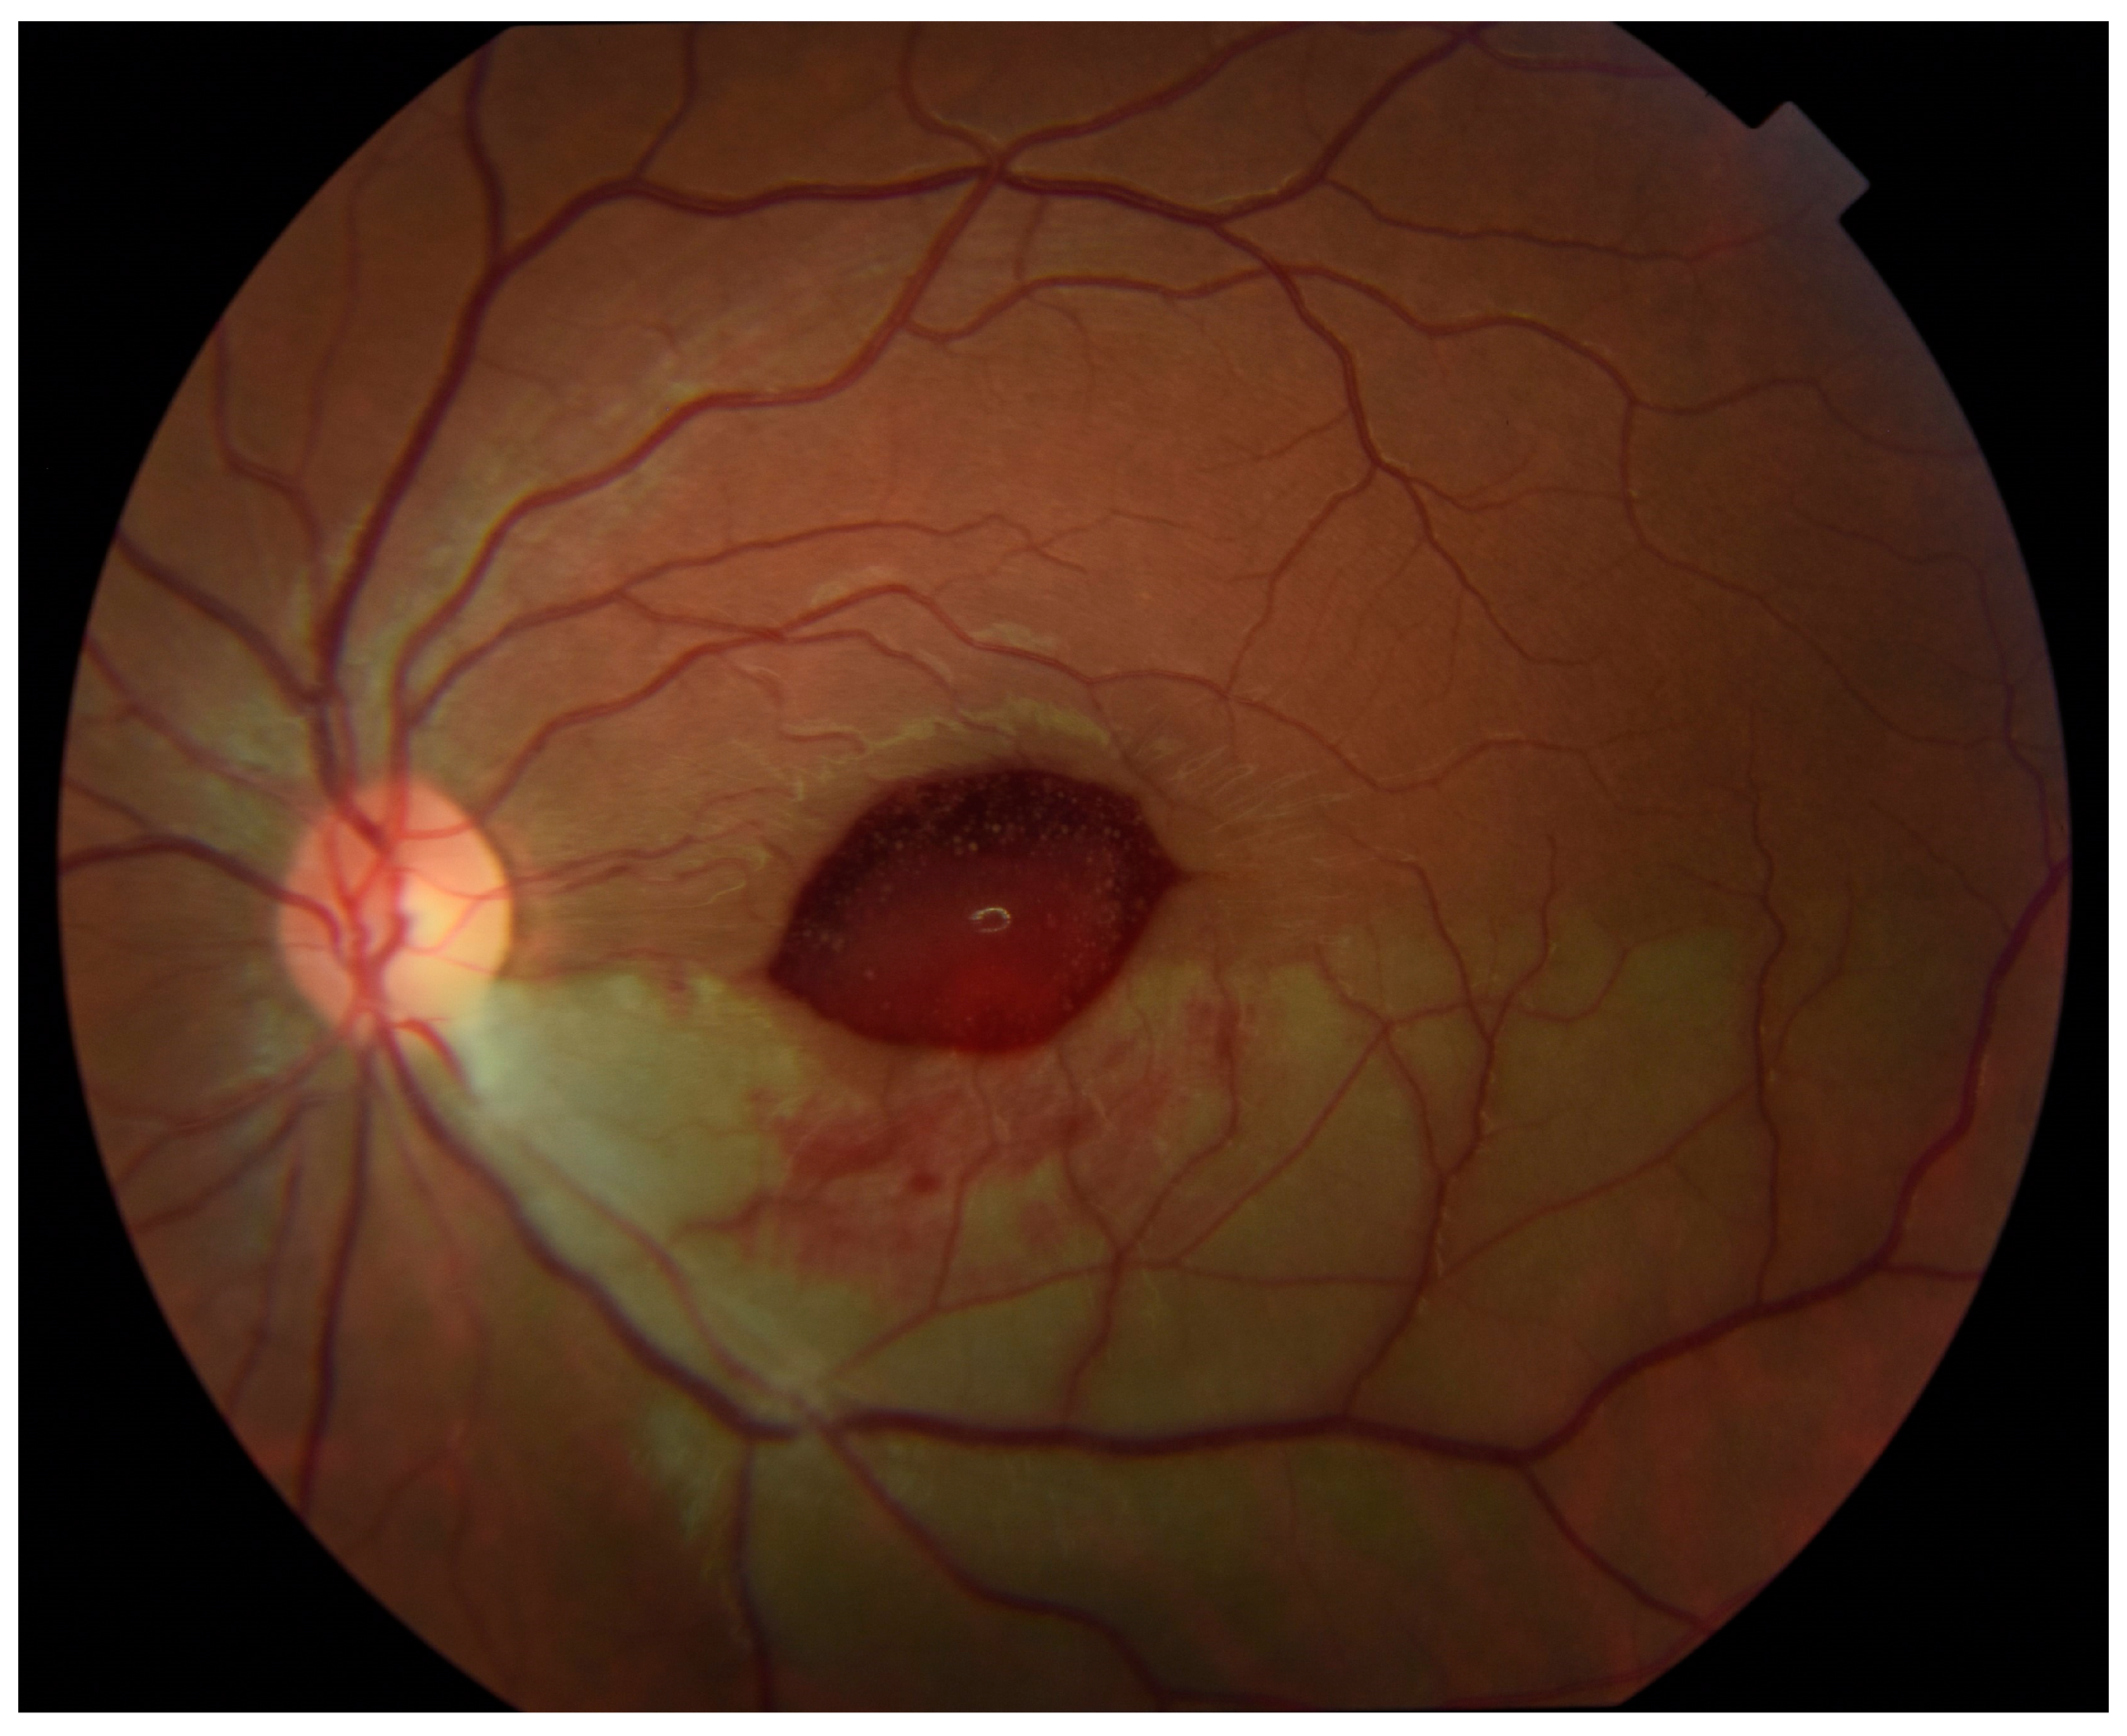

Outpatient follow-up two weeks later revealed visual acuity in the left eye of 20/20 eccentrically. Humphrey visual field 24-2 (Carl Zeiss-Humphrey Systems, Dublin, CA, USA) revealed a superior altitudinal defect, denser nasally. Color fundus photographs showed an ellipsoid area of hemorrhage obscuring the central macula (Figure 3). The patient had not noticed any subjective decrease in her vision so it is unknown exactly when in the period between 24 h and 2 weeks after intra-arterial tPA that this hemorrhage developed.

Figure 3. Color fundus photograph of the left eye at follow-up 2 weeks after administration of tissue plasminogen activator (tPA) shows new ellipsoid-shaped hemorrhage blocking the central macula and slightly improved inferior retinal whitening.